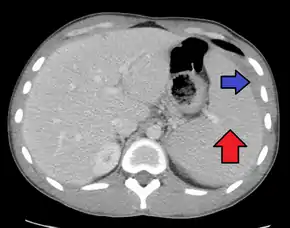

Spleen enlargement is common in the second and third weeks, although this may not be apparent on physical examination. Rarely the spleen may rupture.[24] There may also be some enlargement of the liver.[22] Jaundice occurs only occasionally.[14][25]